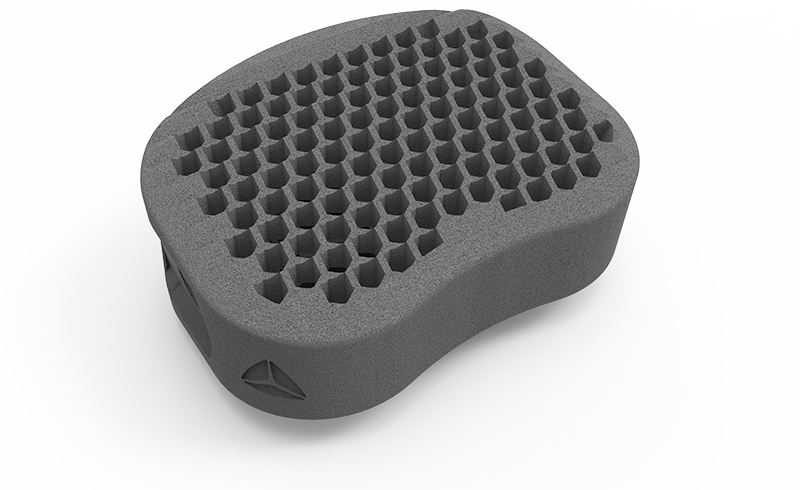

zurückDeltacorCages

Cages

Alle Modelle nun mit der patentierten hygroskopischen Struktur. Diese Kapillarwirkung beeinflusst das Einwachsverhalten positiv ohne Verwendung von autologem Knochen.

HYGROCervicaler Cage aus Titan

Hygro ist ein Unikat auf dem Markt. Wie der Name schon sagt werden durch eine spezielle Anordnung der Lamellen im Inneren des Cages optimale hygroskopische Eigenschaften erziehlt. Eine Fusion wird hierbei erzielt ohne den Cage mit autologem Knochen oder Knochenersatzmaterial zu befüllen.